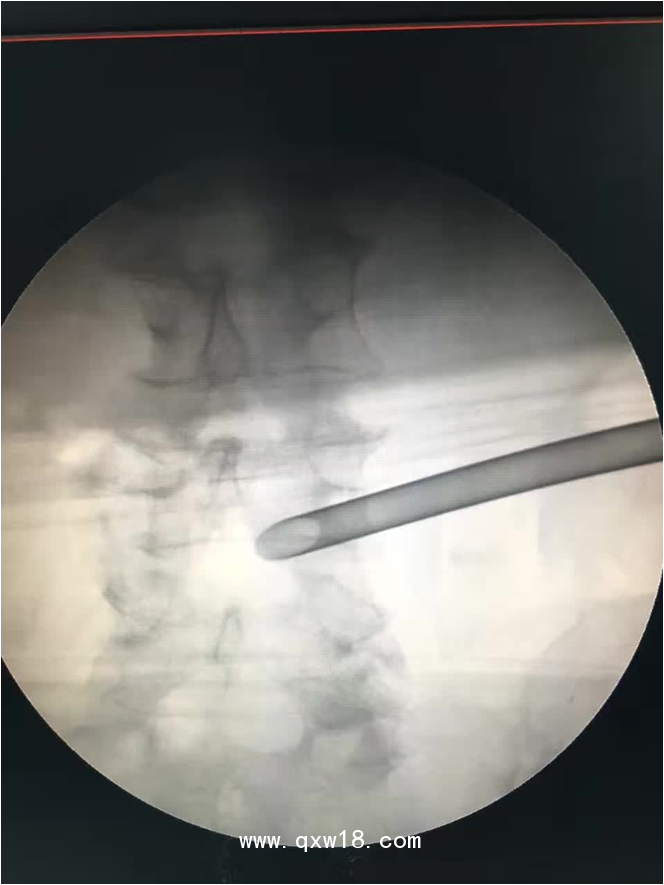

椎間孔鏡品牌椎間孔鏡椎間孔鏡技術椎間孔鏡培訓產(chǎn)品說明:

portant; word-wrap: break-word !important;">椎間孔鏡手術圍手術期注意事項: